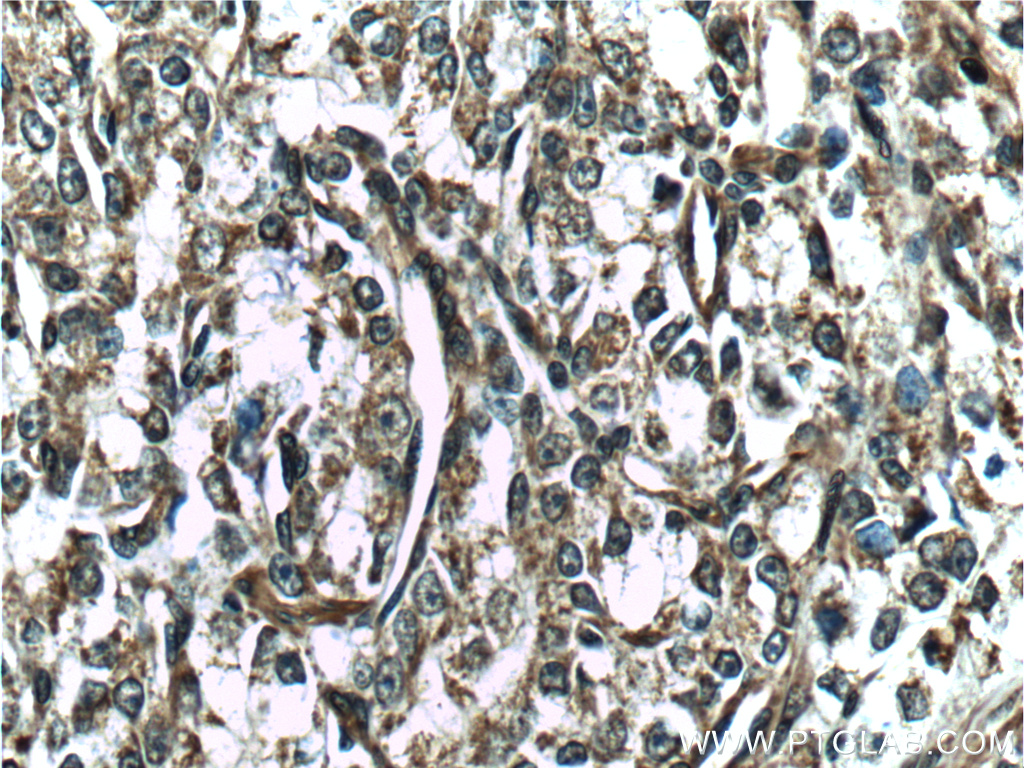

| Positive IHC detected in | mouse colon tissue, human breast cancer tissue, human prostate cancer tissue, human skeletal muscle tissue, mouse skeletal muscle tissue Note: suggested antigen retrieval with TE buffer pH 9.0; (*) Alternatively, antigen retrieval may be performed with citrate buffer pH 6.0 |

26520-1-AP targets Vinculin in WB, IHC, IF/ICC, IF-P, FC (Intra), IP, ELISA applications and shows reactivity with human, mouse, rat, canine samples.

Vinculin belongs to the vinculin/alpha-catenin family. It is an actin filament (F-actin)-binding protein which involved in cell-matrix adhesion and cell-cell adhesion. Vinculin regulates cell-surface E-cadherin expression and potentiates mechanosensing by the E-cadherin complex. It may also play important roles in cell morphology and locomotion. Vinculin is a 117-kDa, 1,066-amino-acid protein which is ubiquitously expressed. Its splice variant, metavinculin (124 kDa), is muscle-specific.